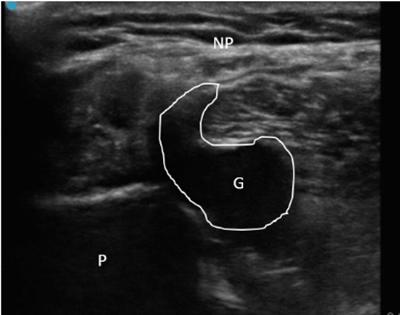

Neuropatía peronea secundaria a ganglión extraneural: revisión de literatura y propuesta de tratamiento. Caso no positivo

Peroneal neuropathy caused by an extraneural ganglion: literary review and treatment proposal. A non-positive case

Este artículo presenta el caso de un paciente de 69 años con una neuropatía compresiva peronea secundaria a un ganglión, inicialmente interpretada como una radiculopatía L5. Este incorrecto enfoque supuso la sobremedicación del paciente, un mal control algésico, la realización de una discectomía L4-L5 innecesaria y una pobre evolución neurológica.

Un enfoque diagnóstico correcto y un abordaje terapéutico precoz habrían supuesto una mayor mejoría clínica e incluso una recuperación neurológica completa del paciente. Por ello, este caso sirve para resaltar: a) el valor de la ecografía en neuropatías periféricas como herramienta diagnóstica y pronóstica y el de la ecografía en gangliones como arma diagnóstico-terapéutica; b) el uso de las pruebas diagnósticas como apoyo a una exploración física exhaustiva, y no como diagnóstico en sí mismas, y c) la importancia de la publicación de casos no positivos para optimizar recursos, evitar repetir errores, reducir el sesgo de publicación y facilitar el inicio de proyectos de investigación.

Tablas y Figuras

Figura 1

Figura 2